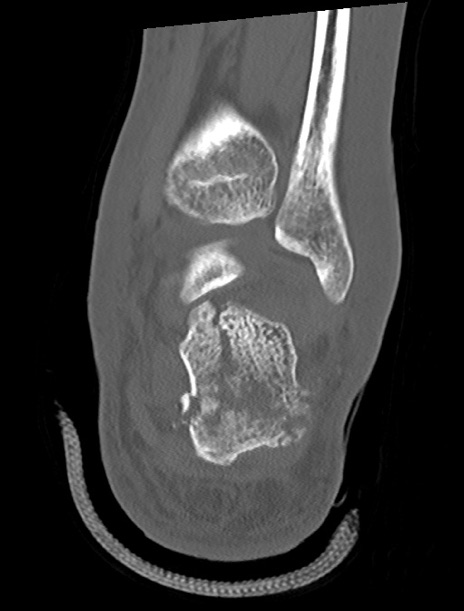

症例37 左足関節CT(冠状断像)

左足関節CT

矢状断像